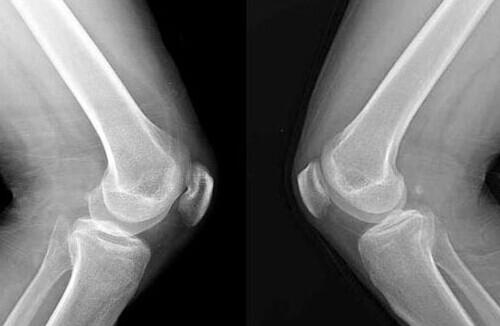

大骨节病多发生在中国、俄罗斯、朝鲜。通常表现为四肢无力、麻木、活动不灵活,手指或足趾等小关节增粗变形,慢慢累及到膝、腕、肘、踝等关节。关节疼痛但不发红,走长路或劳动后疼痛严重。

导致大骨节病的原因可能是土壤中钡、锶过多,导致骨骼脱钙关节病变。相关研究表明硒的缺乏也会引起大骨节病,大骨节病与克山病类似,都是在从东北到西南的低硒地区流行,病区居民处于内外环境低硒状态;在病区补硒可以使大骨节病病情明显下降,但病区补硒后病情并不能完全控制,另有未知的致病因子在起作用。